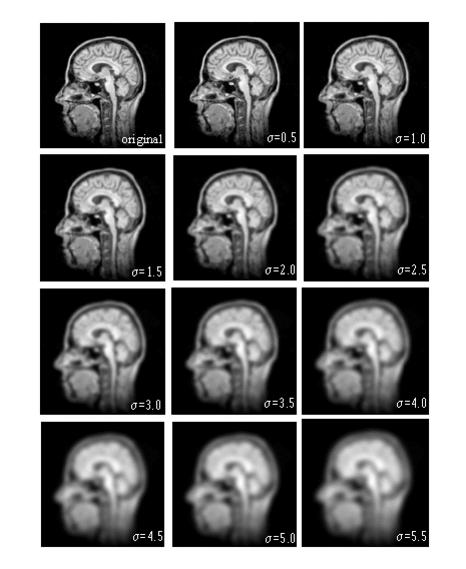

Figure 1. Gaussian Blur algorithm processing

Figure 1 shows a Gaussian scale-space of the sagittal view of a MR head image. The original image is shown in the upper left (). Varying s from 0.5 to 5.5 in steps of 0.5 blurs the other images (from left to right and top to bottom).

Note that as the scale increases, small-scale features are suppressed. For example, at small scales the individual folds of the brain are quite defined, but, as the scale increases, these folds diffuse together resulting in the formation of a region one might define as the brain.